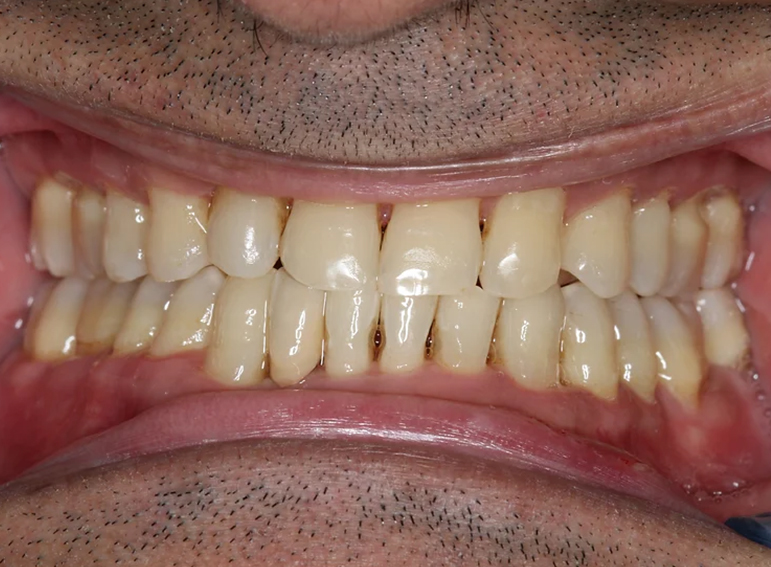

Missing lower incisor replaced with an adhesive bridge.